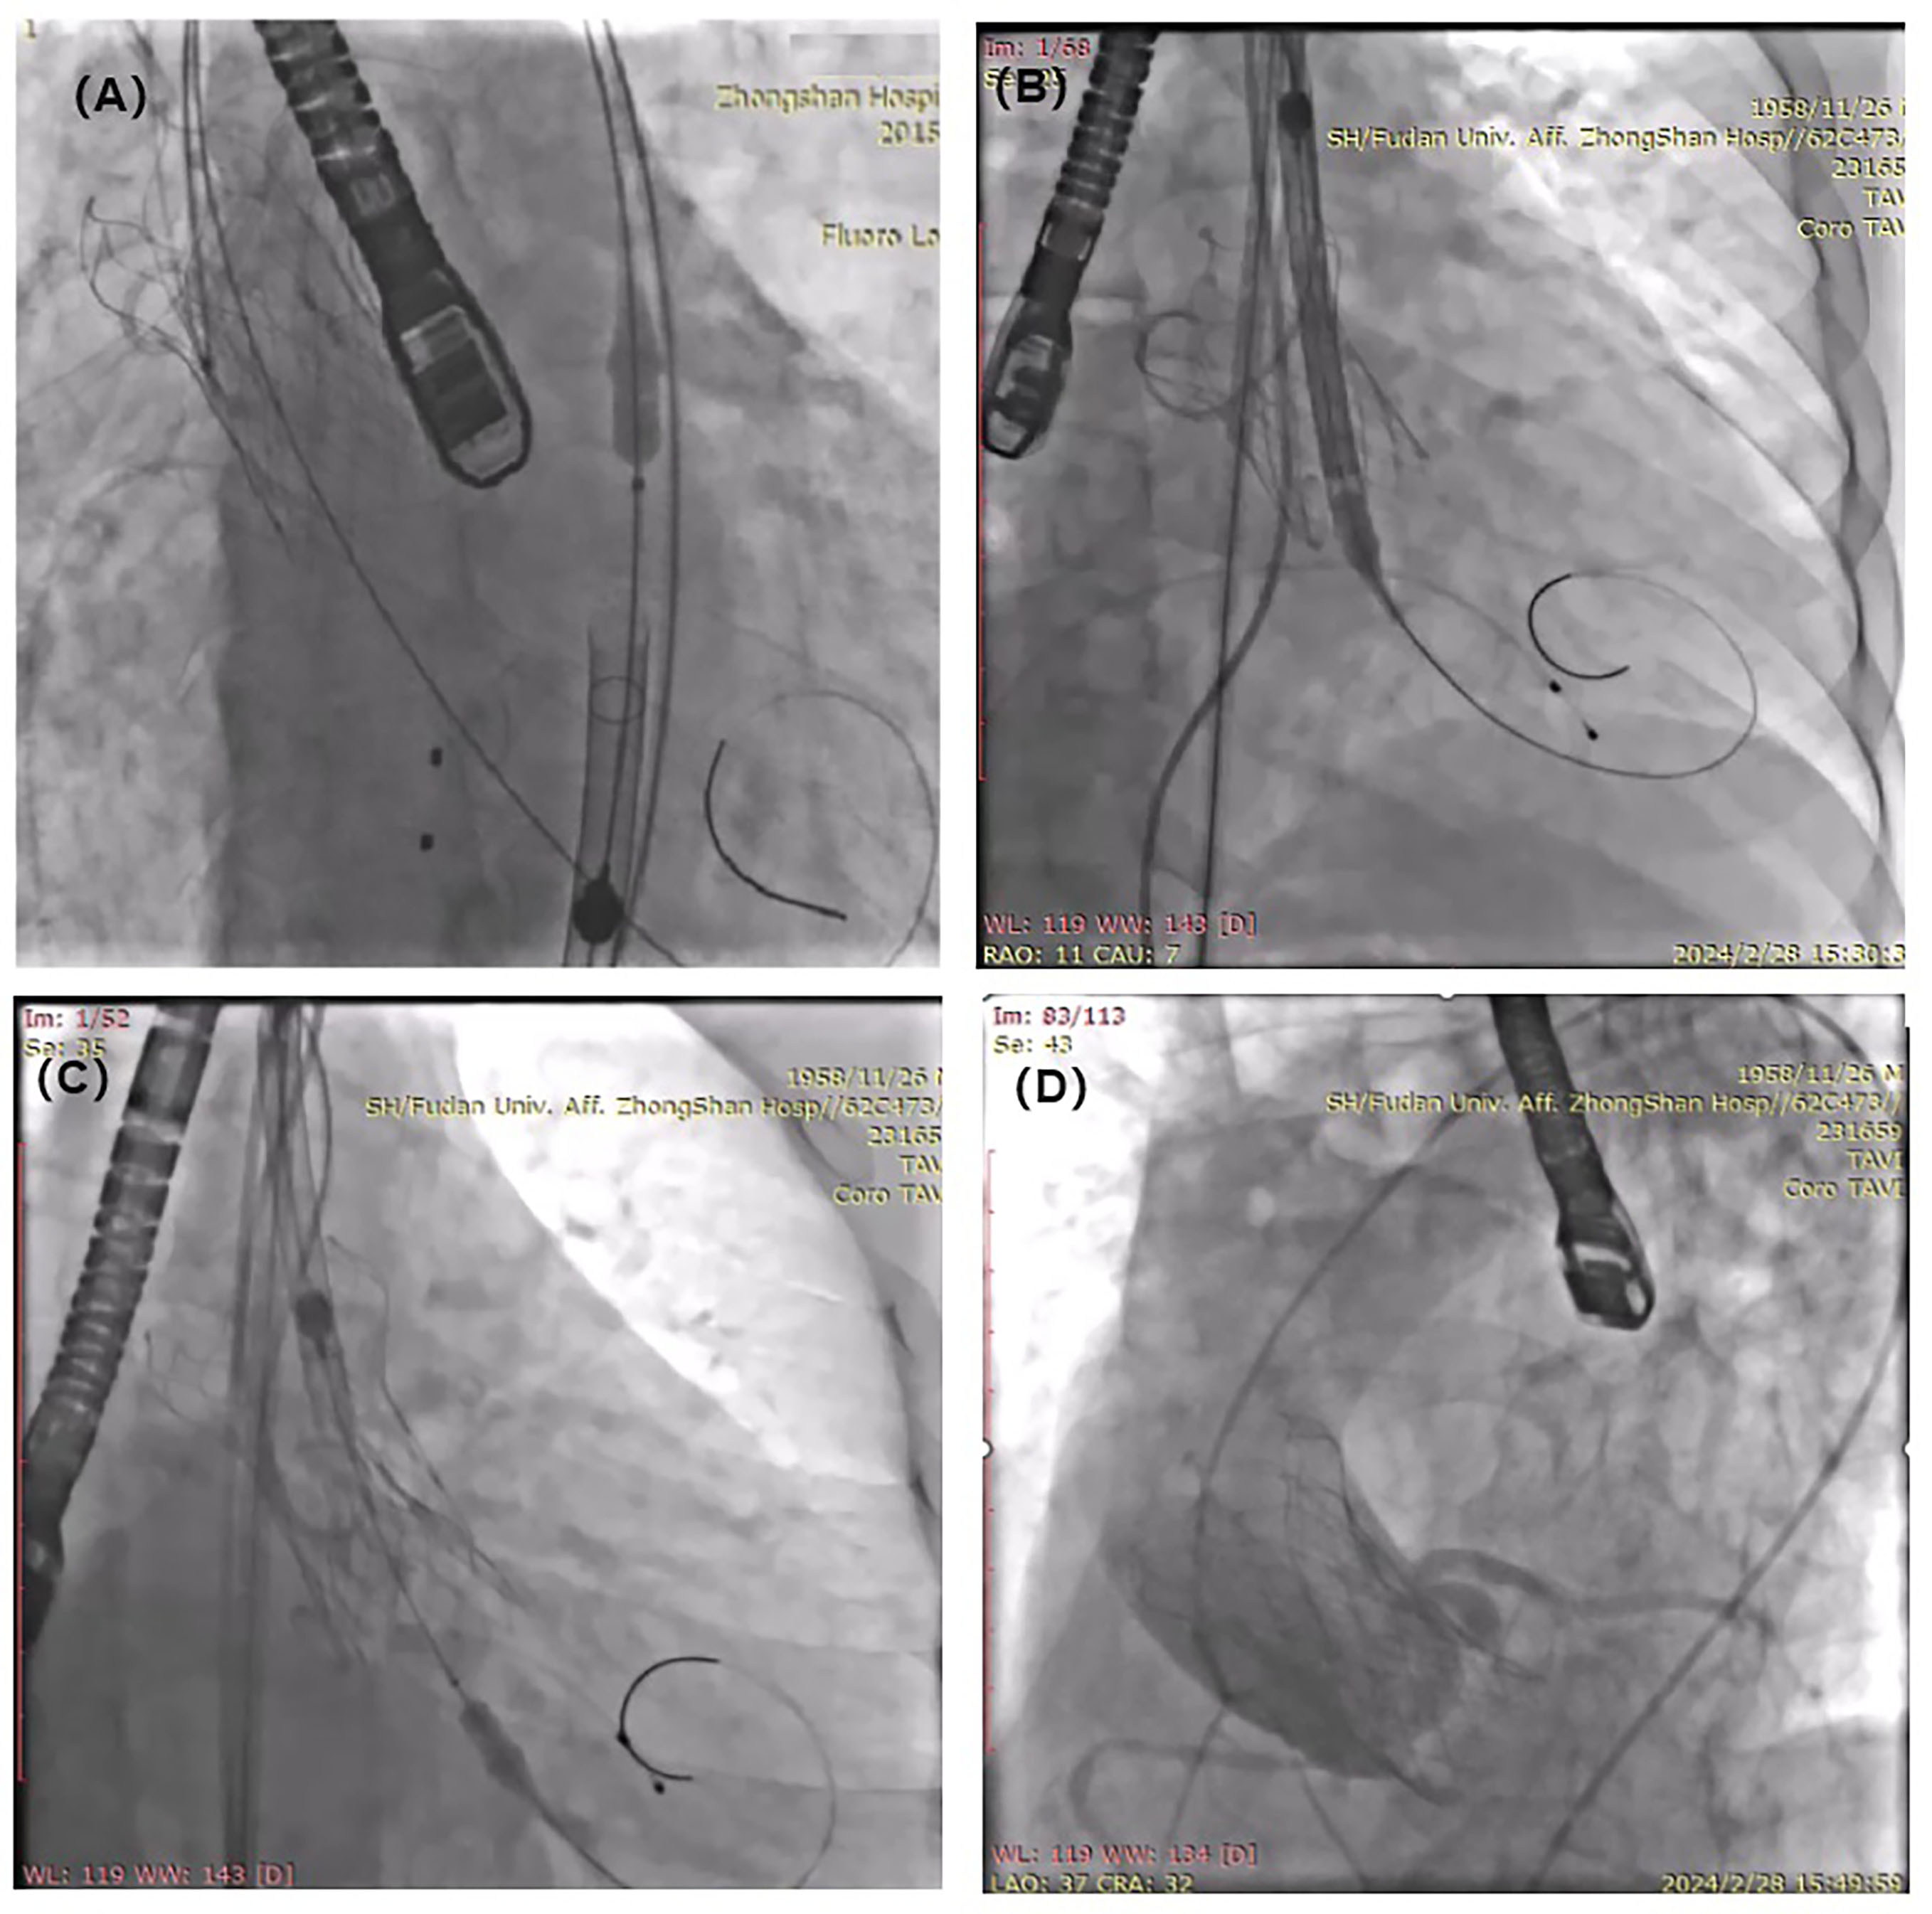

Subsequently, we inserted a 0.035-inch Amplatz Super Stiff wire (Boston Scientific) into the transfemoral accessory 6-French pigtail catheter (Cordis) to enhance the support force and pushed the valve into the bottom of the sinus of Valsalva (Figure 3A and B). Next, another 30-mm self-expanding VitaFlow valve was valve-in-valve released 3 mm below the native annulus (Figure 3C, Video 3). Finally, the first prosthesis, the autologous valve, and the second prosthesis formed a “sandwich” structure, in which the first prosthesis was placed in the bottom of the sinus of Valsalva, preventing the downward movement of the 2 prostheses (Figure 3D). The patient was discharged 4 days after the procedure with good function and no shift of the valves, which was confirmed by echocardiography.